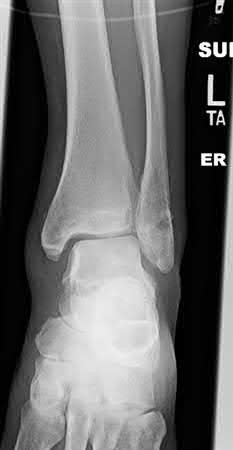

A 25-year-old male sustains an ankle fracture dislocation and undergoes open reduction and internal fixation. He returns to clinic five months following surgery complaining of continued ankle pain and instability with weight bearing. His immediate post-operative AP radiograph is seen in Figure A. Which of the following could have prevented this patient from developing persistent pain?

The patient presents with continued ankle pain and instability following open reduction and internal fixation. The radiograph in figure A demonstrates inadequate restoration of fibular length, likely leading to continued tibiotalar instability.